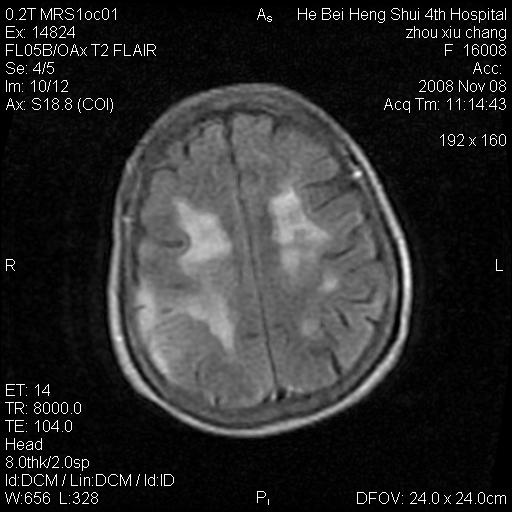

标题: MRI1883:女67岁,半年前曾患脑梗塞,治疗后好转,近3各月精 [打印本页]

标题: MRI1883:女67岁,半年前曾患脑梗塞,治疗后好转,近3各月精

女67岁,半年前曾患脑梗塞,治疗后好转,近3各月精神恍惚。

两种可能:1,转移瘤,2,脑炎,建议增强扫描

多发硬化(年龄不太支持)待排转移瘤

转移瘤?淋巴瘤?

形态及整体病灶看起来首先考虑转移瘤或淋巴瘤,但奇怪的是多个病灶周围均未见显著的水肿区,这不符合这两个肿瘤的特点,结合ct表现及患者病史有个人考虑是否有皮层下动脉硬化性脑病伴多发胶质增生可能.

考虑  皮层下动脉硬化性脑病伴脑炎或

不像占位性病变,考虑脱髓鞘改变

脑转移瘤?

1皮层下动脉硬化性脑病,2胶质增生。

皮层下动脉硬化性脑病伴脱髓鞘改变!

脑白质病

不除外转移瘤,建议增强

支持:皮层下动脉硬化性脑病伴脱髓鞘改变。